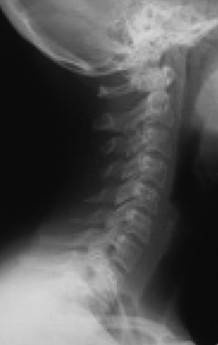

Еще одно сообщение Phys-Org: руководитель службы пластической и реконструктивной хирургии в американской университетской клинике Говард Лэнгстайн (Howard Langstein) на основании своих многочисленных исследований утверждает, что с возрастом происходит изменение угла нижней челюсти (показанные желтым цветом), длина и высота самого тела челюсти (рис. 10).

Иллюстрация к книге — Биогимнастика для лица: система фейсмионика [i_013.jpg]

Рис. 10. Череп молодого человека